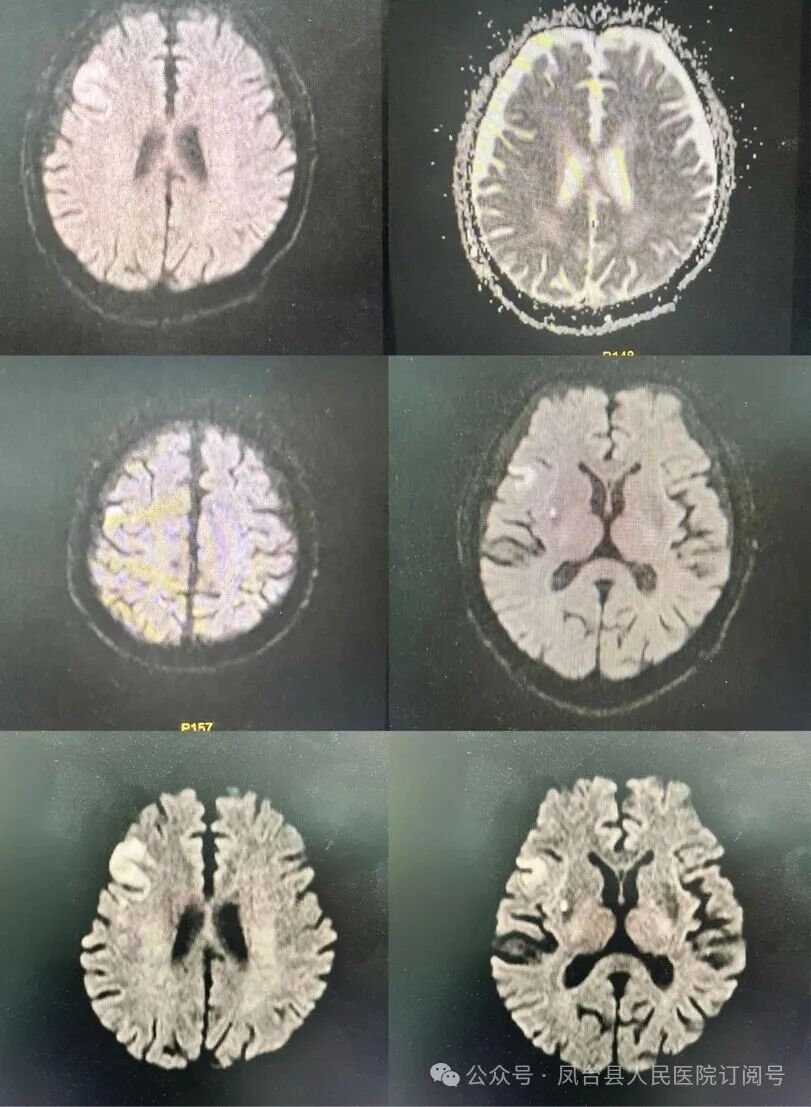

在溶栓病房接受治疗的第二天,患者已能够独立行走,实现完全康复。在神经内科卒中团队查房时,患者及其家属向医护人员表达了深切的感激之情,那一刻,全体医护人员内心充满了无比的成就感。随后的磁共振检查结果也显示,患者多发脑梗死,其中右侧额叶、海马及基底节区的病灶为新近发生的梗死。